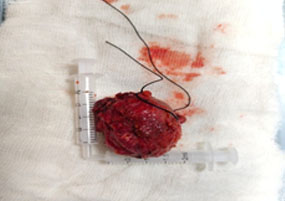

TDC is the most common congenital anomaly related to the thyroid gland. In a TDC, papillary carcinomas typically present as swellings along the midline of the neck, which move with deglutition and tongue projection. Less than 1% lof all TDC cases present with papillary carcinomas. This type of pathology has a good prognosis and can be successfully managed with cyst removal (Sistrunk procedure) and careful follow-up. Thyroidectomy, neck lymph node dissection, or adjuvant treatments are not required in most cases.